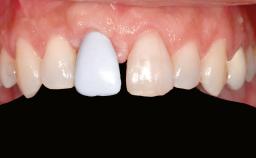

Prosthesis Type FDP

Lip Line No exposure of papillae Exposure of papillae Full exposure of mucosa margin

Periodontal Phenotype Low-scalloped, thick Medium-scalloped, medium-thick High-scalloped, thin

Shape of Tooth Crowns Rectangular Triangular